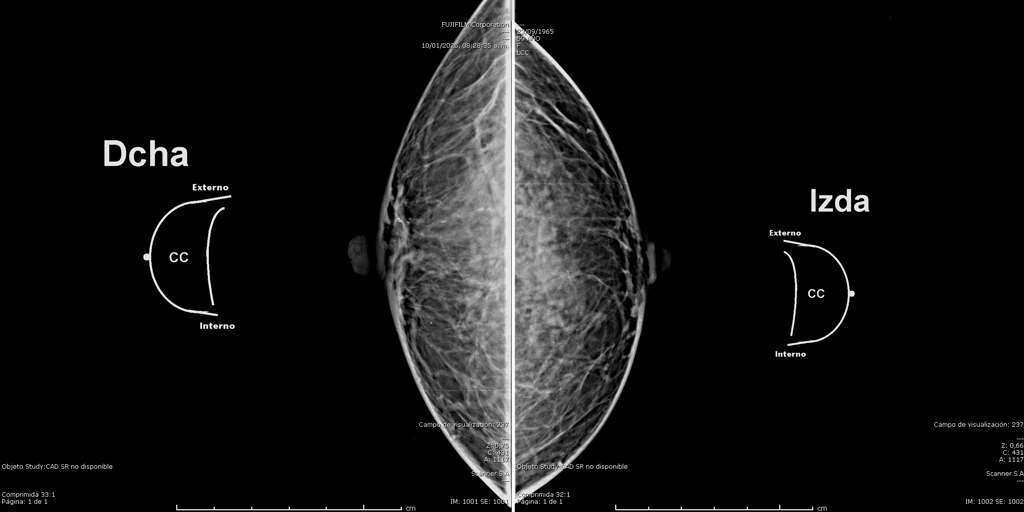

Mamografía Digital

La mamografía es un estudio de diagnóstico por imagen que utiliza bajas dosis de rayos X para obtener imágenes detalladas del tejido mamario. Es una herramienta fundamental para la detección temprana del cáncer de mama y otras patologías mamarias, incluso antes de que sean evidentes al tacto o generen síntomas. Su uso regular en controles preventivos permite salvar vidas al facilitar diagnósticos oportunos y tratamientos más efectivos.

En SCANNER S.A, nuestros equipos digitalizados permiten detectar cambios mínimos en el tejido mamario con alta claridad, permitiendo asi tener un diagnostico preciso y entregar unos resultados reales a nuestros pacientes.